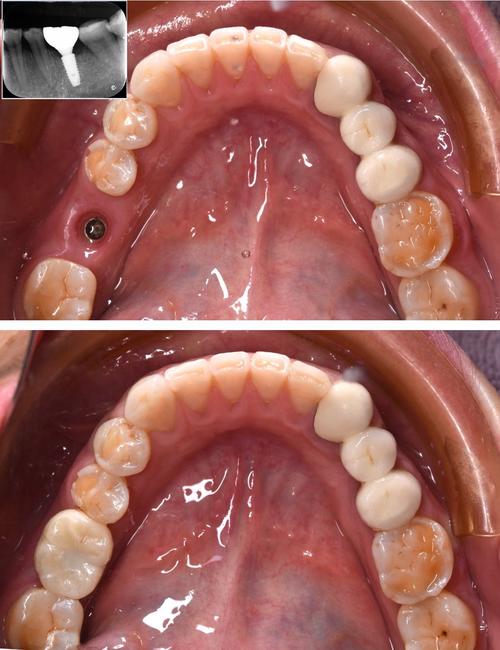

牙槽骨是支撑种植体的“地基”,若骨量不足,种植体易松动、脱落,甚至导致种植失败,生物膜通过“屏障作用”将骨缺损区域与周围软组织隔离,阻止成纤维细胞(易形成疤痕组织)快速侵入,为骨细胞(成骨细胞)的增殖和分化提供“专属空间”,生物膜可配合骨移植材料(如人工骨、自体骨),引导骨细胞沿着移植材料生长,逐步填补骨缺损,增加骨量和骨密度,确保种植体获得足够的骨支持,在即刻种植(拔牙后立即种植)中,牙槽窝常存在不规则骨缺损,此时植入生物膜+骨移植材料,可显著提高骨结合质量和稳定性。

种植牙不仅要“用得好”,更要“长得美”,尤其在前牙美学区,牙龈形态、牙龈乳头的高度直接影响笑容美观度,当患者存在牙龈萎缩、牙龈袖口形态不佳时,生物膜可引导牙龈成纤维细胞和上皮细胞有序生长,促进牙龈组织附着,形成自然、健康的牙龈袖口,避免种植体周围“黑三角”或牙龈退缩等问题,生物膜中的胶原蛋白等成分还能促进血管生成,加速软组织愈合,减少术后出血和感染风险。